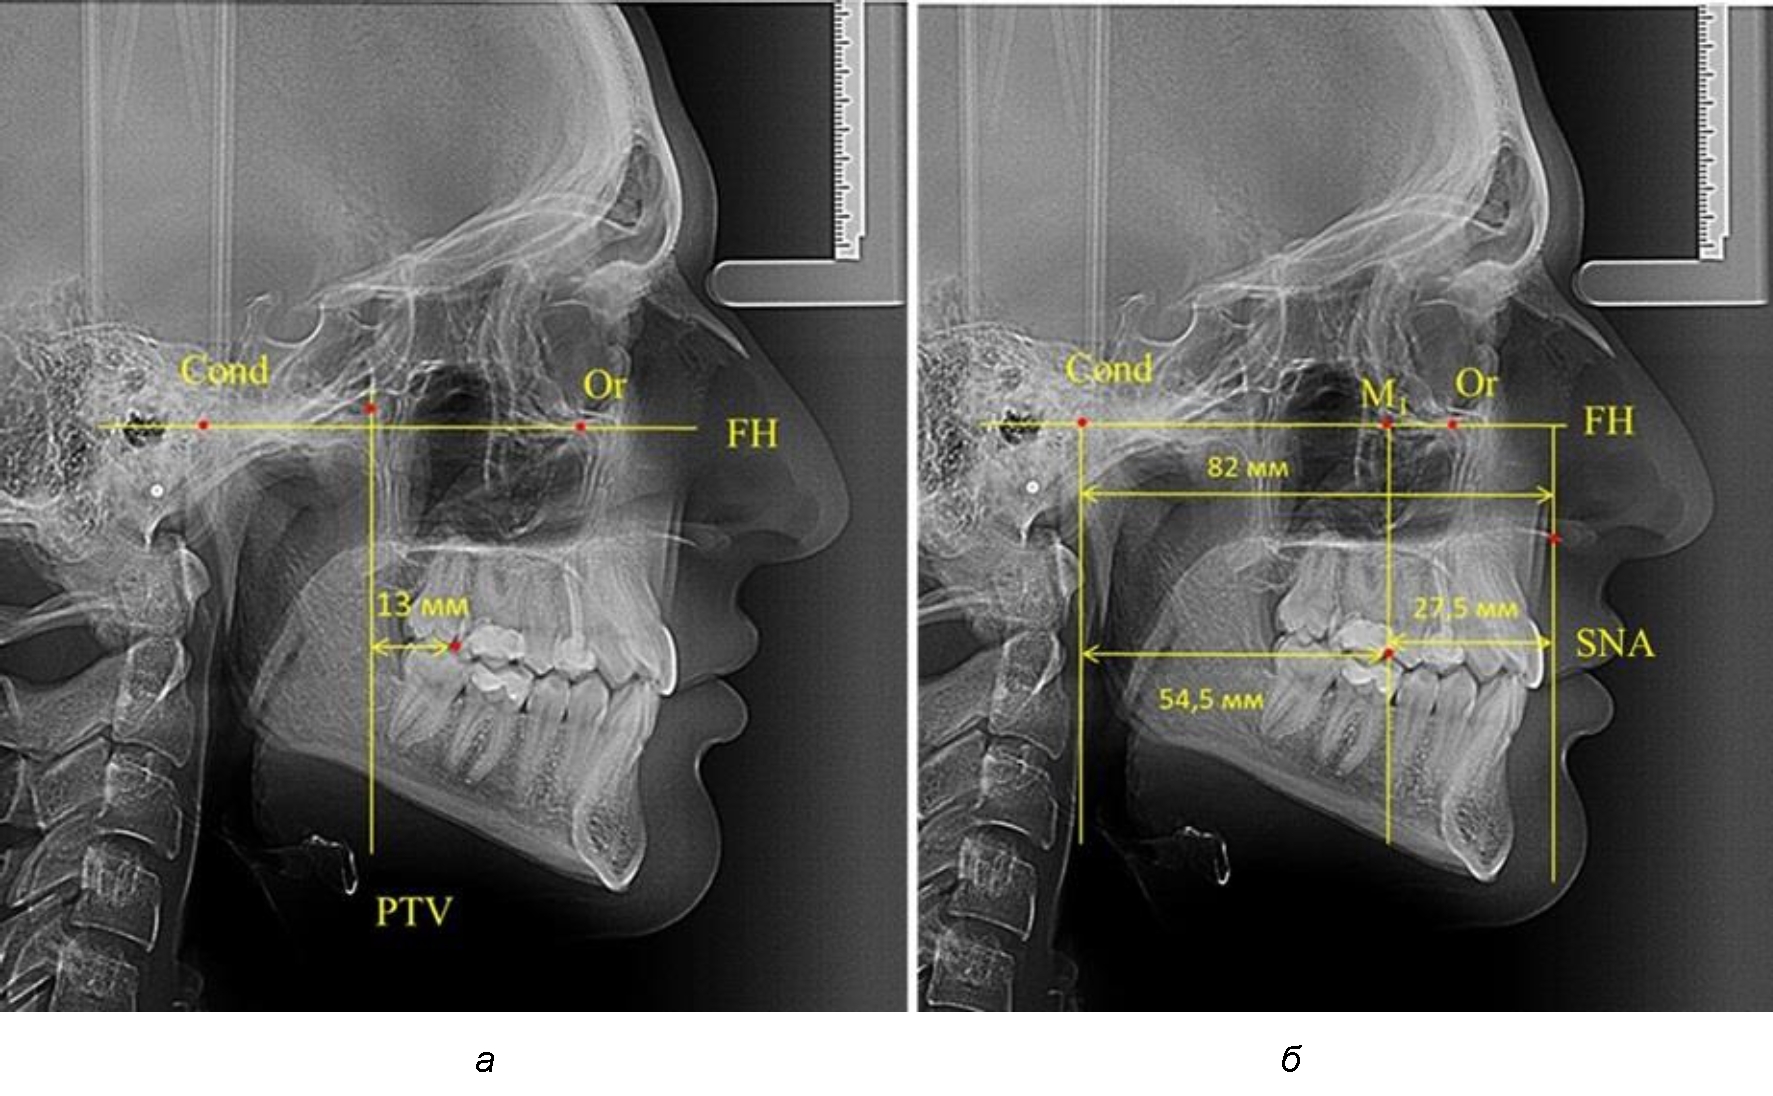

При проведении анализа к Франкфуртской горизонтали проводили передний и задний перпендикуляры. Передний спинальный перпендикуляр проходил через выступающую точку передней носовой ости (spina nasalis anterior – SNA), а задний суставной перпендикуляр опускали из кондилярной точки Cond. Молярный перпендикуляр проводили через медиальную поверхность первого постоянного моляра. Указанная вертикаль отделяла замещающие зубы постоянного прикуса от добавочных зубов (постоянных моляров), что вполне логично для анализа положения первых постоянных моляров в гнатическом комплексе (рис. 1).

Рис. 1. Метод определения положения первых верхних моляров по Ralph E. McDonald (а) и по предложенному методу (б)

Так, при расстоянии от крыловидной вертикальной плоскости PTV до дистальной поверхности верхнего первого постоянного моляра в 13 мм сагиттальный размер гнатического отдела был 82 мм. При этом отношение кондилярно-спинального расстояния к кондилярно-молярному размеру (54,5) было близким к коэффициенту 1,5, что представлено на рис. 2.